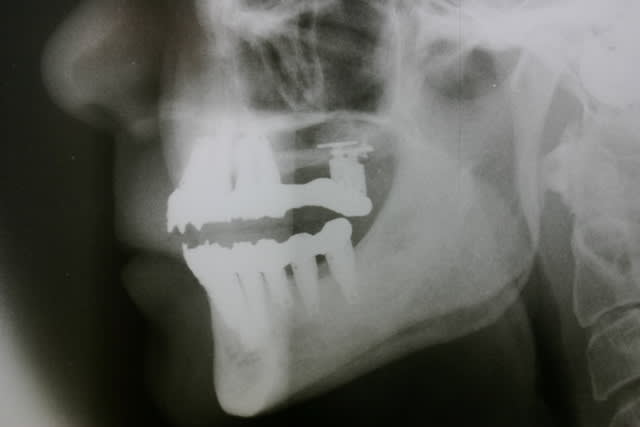

Pp vous remet bien le bonjour à tous et part en vacances après s'être bcp trop amusé ces temps-ci...

PS Désolé pour les kissing implants en 12 13 ...